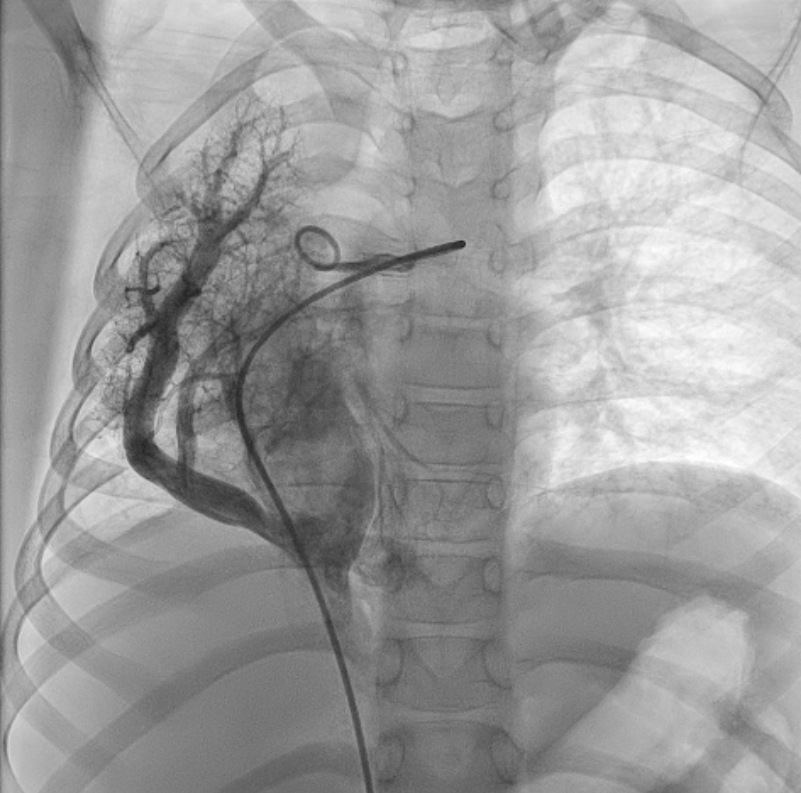

An 8-year-old girl presented with persistent pneumonia of a 1-month duration and right lower zone opacity on chest x-ray. Computed tomography of her thorax revealed right lung hypoplasia with partial anomalous pulmonary venous drainage (PAPVD) of the right pulmonary veins into the inferior vena cava. Two prominent aortopulmonary collaterals (APCs) supplying the right lung were noted—one from the descending thoracic aorta (DTA) and one from the celiac artery—along with 2 minor APCs from the DTA (Figure 1). These features were consistent with Scimitar syndrome, named after its visual resemblance to the Turkish sword (Video 1, Figure 2).

Following resolution of pneumonia, the child underwent cardiac catheterization, which confirmed dual arterial supply to the right lung via the right pulmonary artery and APCs. It was decided to redirect flow and reduce shunting using vascular plugs. First, femoral access was obtained with a 5F catheter. Next, a digital subtraction aortogram was performed with a 5F pigtail catheter. The prominent APC from the DTA measured 3.1 mm; it was hooked with a 5F Judkins right (JR) guiding catheter. A 4 x 6-mm Amplatzer Vascular Plug II (Abbott) was then deployed into the APC under angiographic guidance. The APC from the celiac artery measured 3.2 mm; it was hooked with a 5F JR guiding catheter. A 6 x 6-mm Amplatzer Vascular Plug II was deployed into the APC under angiographic guidance. The prominent APCs were successfully occluded (Figure 3), and post-deployment angiogram showed good position and good flows in the celiac artery and its other branches (Video 2).